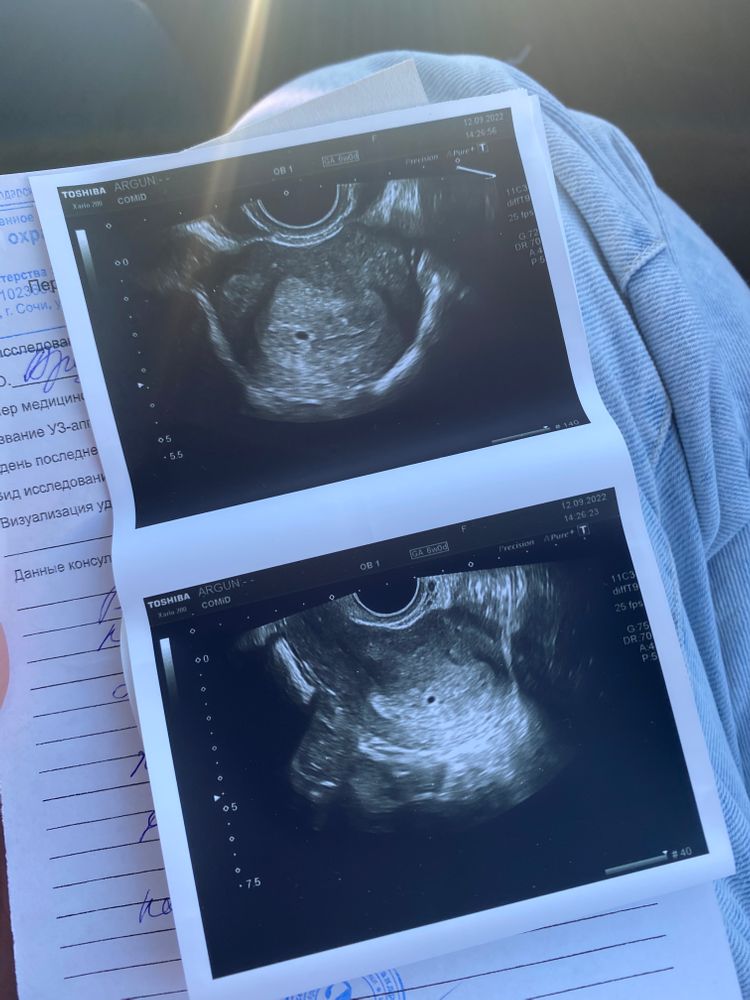

Девочки, хгч вчера утром 1580 нормально для 3-4 недель? Пересдам завтра утром🙏🏻 Прикрепила заключение, пугают замершей. К кого было также?

Мила, без понятия. Говорят, что сроки не совпадают и ставят мне 6 недель и говорят, что должен быть виден эмбрион и слышно сердцебиение. А по факту у меня 3-4 недели

Anastasia, по месячным у вас ровно 6 недель? Овуляцию отслеживали? Судя по хгч у вас только только вот как раз и плодное яйцо стало заметно, это нормально, что с таким хгч нет ни эмбриона, ни сердцебиения! А уровень хгч зависит от овуляции и имплантации, они у вас скорее всего были позже, чем у большинства! Тут главное динамика во всем